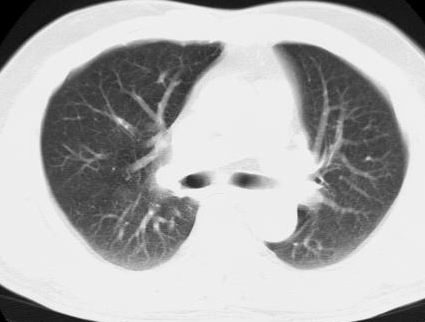

标题: CT15869:男性,71岁,因咳嗽而就诊,请讨论右上肺病变性质 [打印本页]

标题: CT15869:男性,71岁,因咳嗽而就诊,请讨论右上肺病变性质

患者,男性,71岁,因咳嗽而就诊,

典型的右肺中心性肺癌并纵隔淋巴结转移

右肺中心性肺癌并纵隔淋巴结转移可能性大!

考虑右肺中心性肺癌并右肺门及纵隔淋巴结转移。